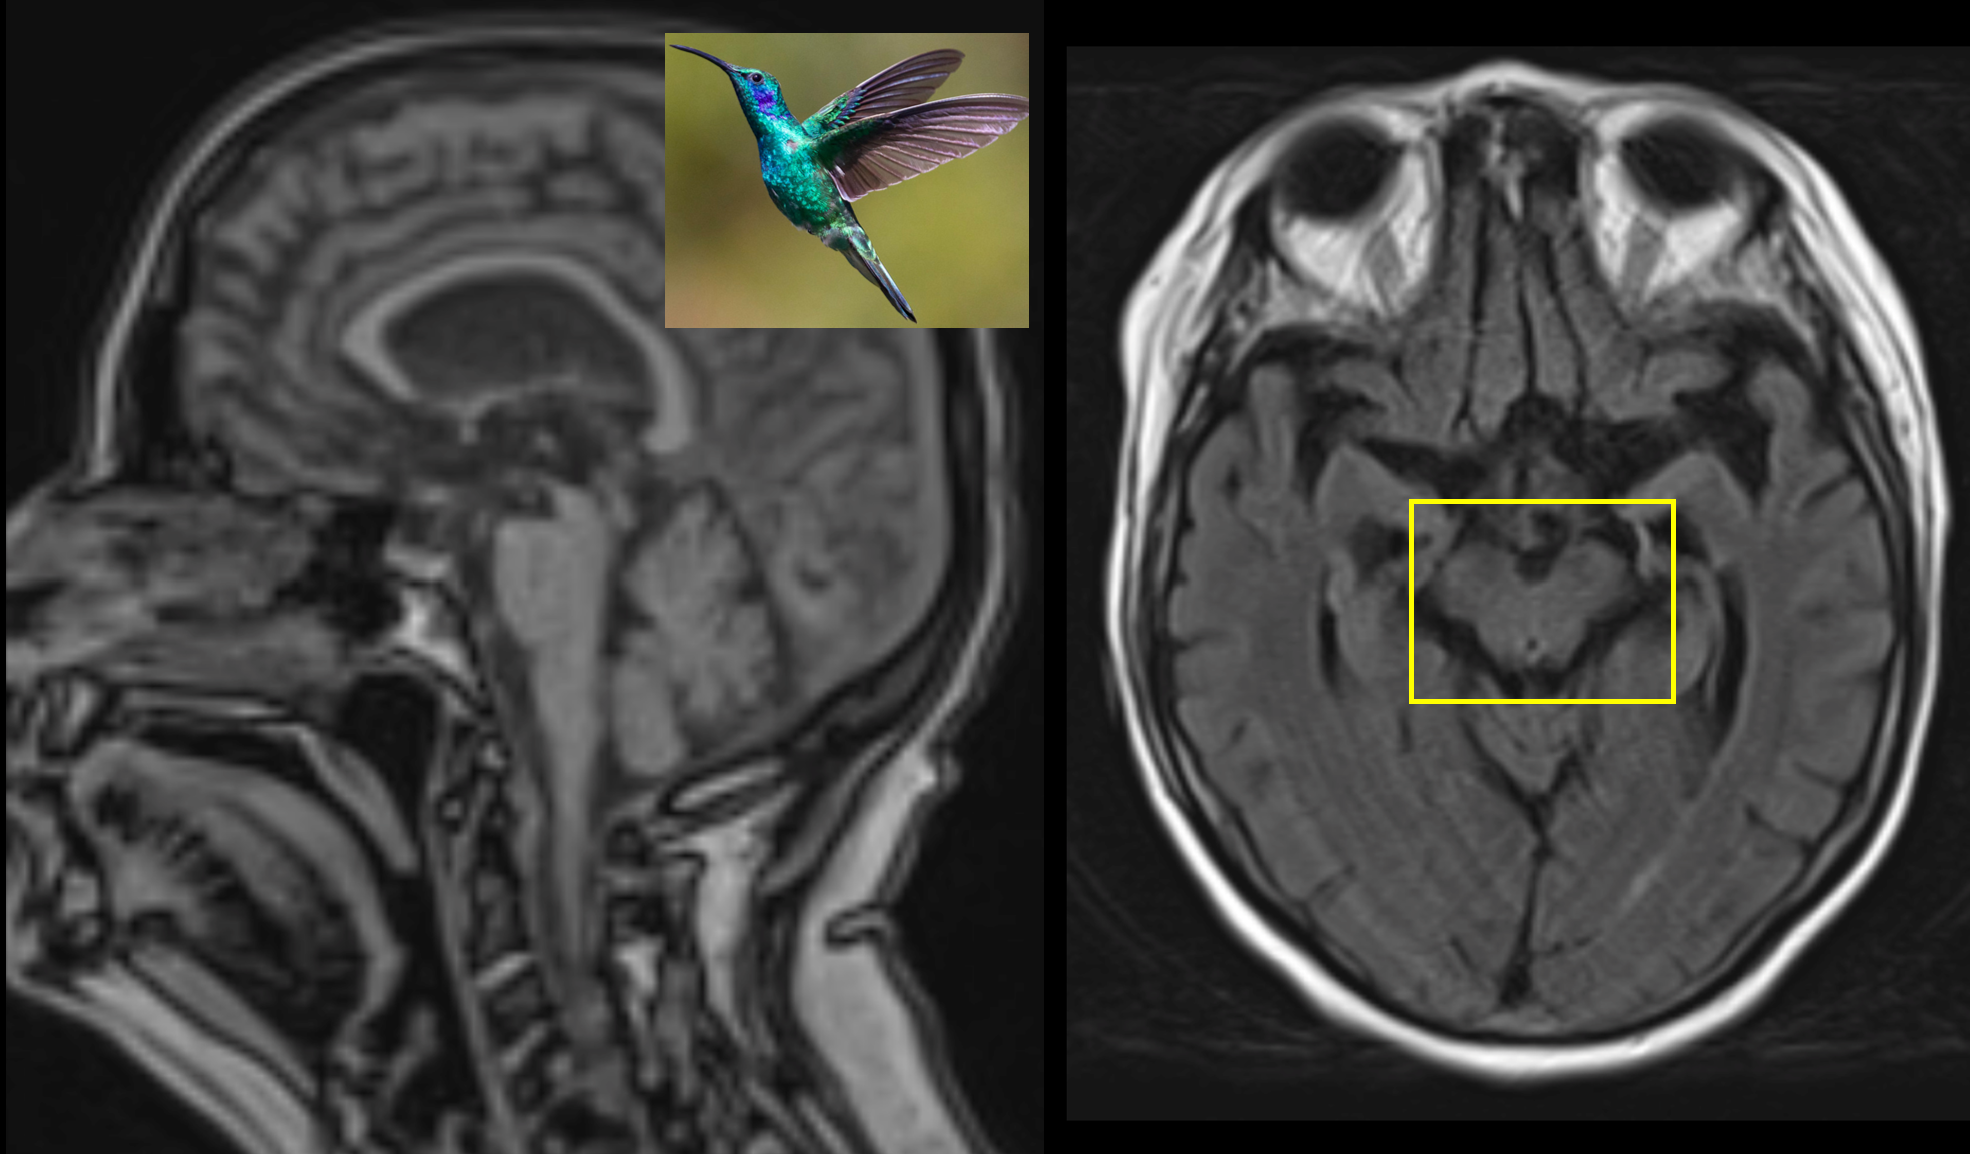

Background

This study explored whether Myelin Water Imaging could detect myelin injury in Anti-NMDA receptor autoimmune encephalitis (NMDAr-AIE), where traditional neuroimaging is often normal. Myelin Water Fraction (MWF) quantifies myelin content by distinguishing myelin sheath water from other brain water compartments.

Methods

Adult participants with confirmed NMDAr-AIE diagnoses and healthy controls (HC) underwent 3T brain MRI (Magnetic Resonance Imaging) including MWF mapping. Participants were recruited after discharge from the hospital. Mean MWF was calculated for 4 white matter regions of interest (ROI). MHI (Myelin heterogeneity Index) was calculated by dividing the MWF standard deviation by the mean MWF. Patient demographics, clinical assessments, treatment, and outcomes were collected.

Results

Fig. 1 Myelin Water Imaging of two selected patients

Screenshot 2025 06 01 at 12.05.23 pm

Myelin Water Imaging showed no myelin pathology in five NMDAr-AIE patients, with MWF and MHI values comparable to HC, suggesting that myelin pathways are relatively preserved post-recovery from AIE. Moving forward, we aim to continue recruiting healthy controls, patients post-recovery and those experiencing active disease to determine if there are any MWF abnormalities throughout the disease course. Future studies are needed to assess MWF changes in other antibody-mediated encephalitides.